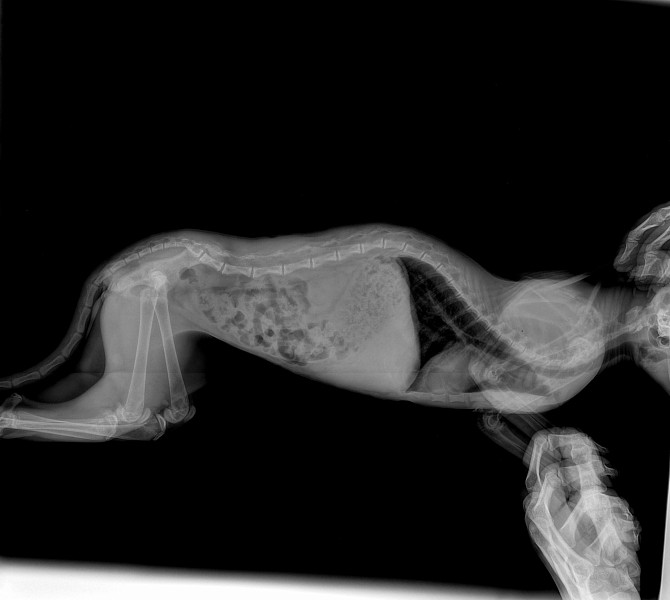

Здравствуйте, у нас сфинкс, девочка 7 мес, стерилизована. питается натуральной пищей+ витамины. Около месяца назад начали замечать малоподвижность, хождение маленькими шажками, с трудом забирается на свои любимые места. Травм не было. Тазовые конечности поджимает под себя. Мы сдали кровь:Мочевина завышена-16.6, щелочная фосфатаза - 558, кальций 1.76, фосфор 2.07. Сказали скорей всего вторичный гиперпаратиреоз. Сделали рентген, снимки прикреплю. В снимках написали еще лордоз в поясничном-крестцовом отделе. Что это?Лечится ли, могло ли это быть тоже последтвием вторичного гиперпаратиреоза?

Добрый день. Да, действительно по рентген снимкам у вас подозрение на алиментарный гиперпаратиреоз. Лордоз является последствием гиперпаратиреоза. Вам рекомендовано перейти на промышленный корм премиум класса, ограничить физические нагрузки, а именно прыжки с высоты. При боли можете принимать обезболивающие препараты типа Неболин вет/Мелоксивет по 0.05 мг/кг 1 р/д после кормления. Касаемое различных витаминов и кальция, тут вопрос спорный, их прием необязательный. На данном этапе с лордозом делать ничего не надо. В будущей если вдруг проявятся признаки неврологического дефицита (шаткость походки, малоподвижность) сделайте магнито-резонансную томографию (МРТ) грудно-поясничного отдела позвоночника. После описанных рекомендаций переделайте рентген снимки через 3 мес.